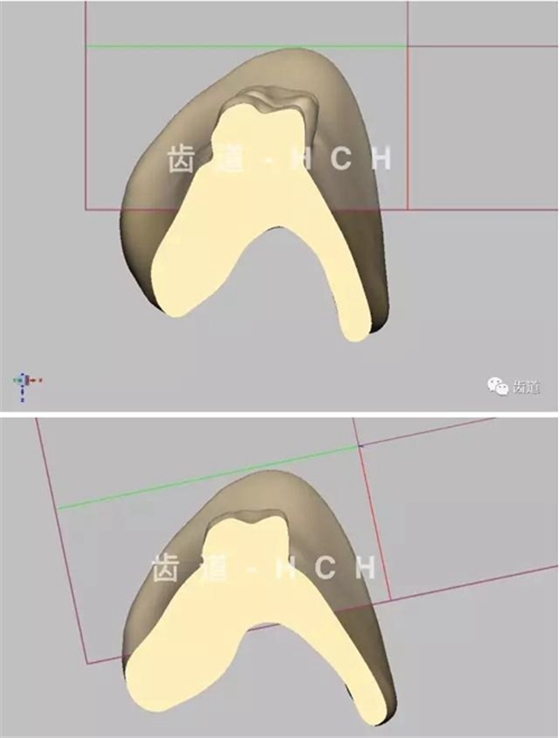

首頁義齒技術(shù) 標(biāo)準(zhǔn)全口義齒模型截圖 科貿(mào)嘉友收錄

標(biāo)準(zhǔn)全口義齒模型截圖 科貿(mào)嘉友收錄